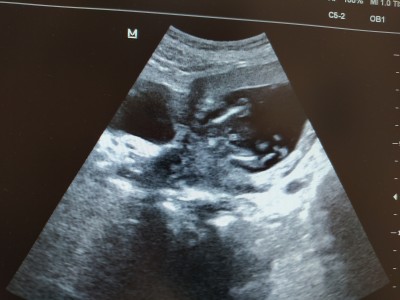

kızlar 12 haftada demiştim ya tahmini cinsiyet söyledi bugün 15 haftaligim gittim yüzde yüz kesin erkek dedi hazırlığa baslayabilirmiym dedim evet dedi net erkek devlet hastanesi bu arada ilk tahmini yine devltte aynı doktorm yapmsti artık kesin gözüyle bakayım mi sizce eşime soylim mi :)

valla bnde şasirdm canm tam 12+1 erkeğe çok benziyor dedi ikili taramayı yapan doktorlarda çıkıntı var erkek dedi ama emin olmak için bekle dedi aslında bugün tam 14 haftalık ama doktorum önceden tarihimi bir hafta öne almıştı böyle devam edecz demisti ondn 15 haftalık olarak devam ediym

aynen degismedi yine aynısini dedi bacak arasında gördüm değişme heralde bundn snra

ilkine 12 erkeğe benziyor dediler 14 özelde kıza snra 17 devlette kordon var erkege benziyor dediler snra gostermedi  en son 24 kıza benxiyor dediler hiç birinde kesin demediler hep 60 70 yüzde verdiler en son prensesler gibi kızım oldu bunda hiç kız demediler 5 defa 4 doktorda erkek dedi en son işte kendi doktorum yüzde yüz kesin erkek dedi değişmese iyi:))

Erkek bebekler daha net gösteriyor. 2.oğlum olacak şimdi.  Ortanca kızım var tek bir defa kız olabilir dediler bir daha da göstermedi :)